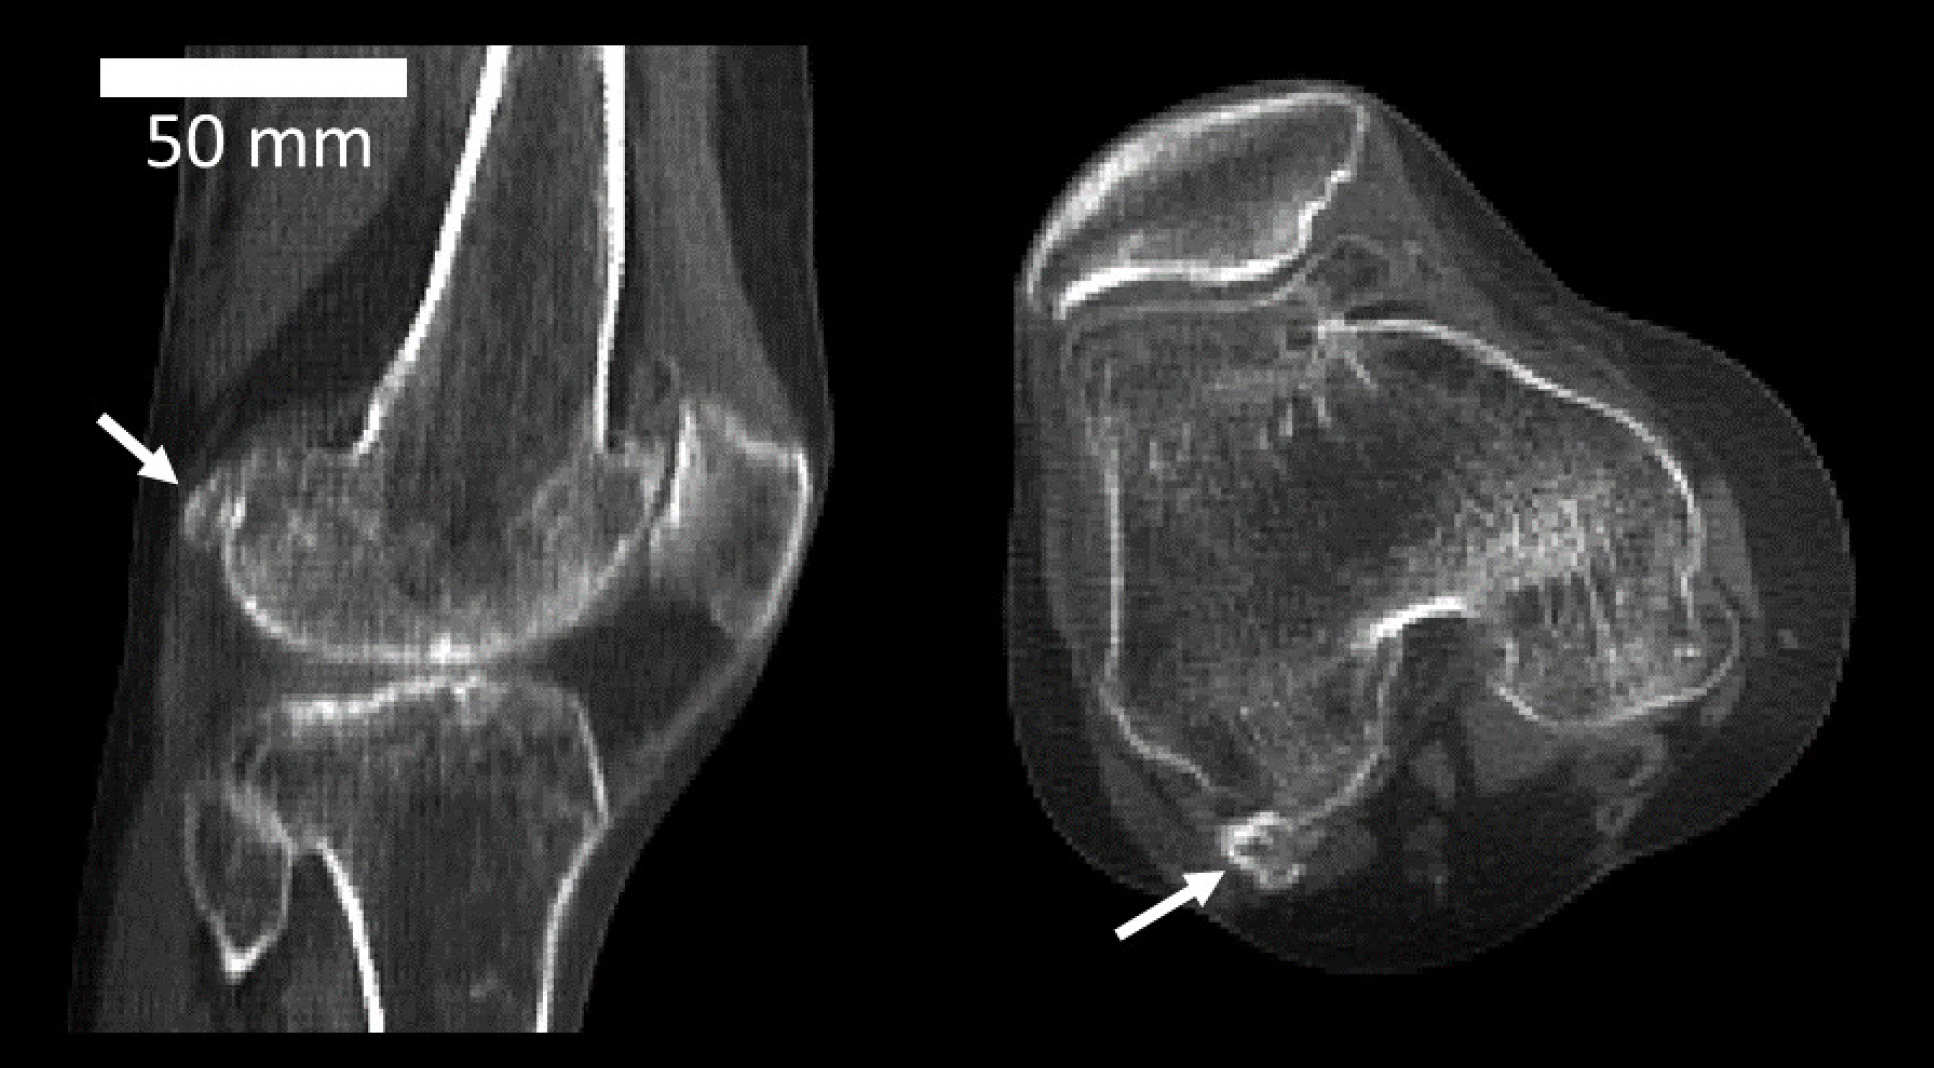

CT scan of a knee joint with fabella

The tiny fabella bone is found in a knee joint tendon

Dr Berthaume added: “The average human, today, is better nourished, meaning we are taller and heavier. This came with longer shinbones and larger calf muscles – changes which both put the knee under increasing pressure. This could explain why fabellae are more common now than they once were.”CT scan of knee joints with fabellaeNot all people have fabellae, however, and there is likely a genetic component controlling the ability to form one – but for those who can form a fabella, this increased mechanical forces might drive their formation.